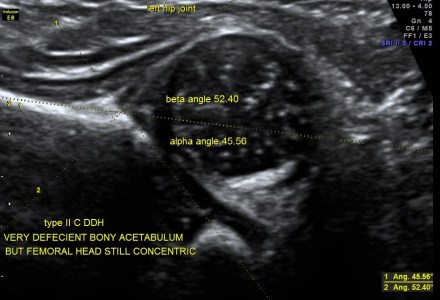

Developmental Dysplasia of HIP (D.D.H.)